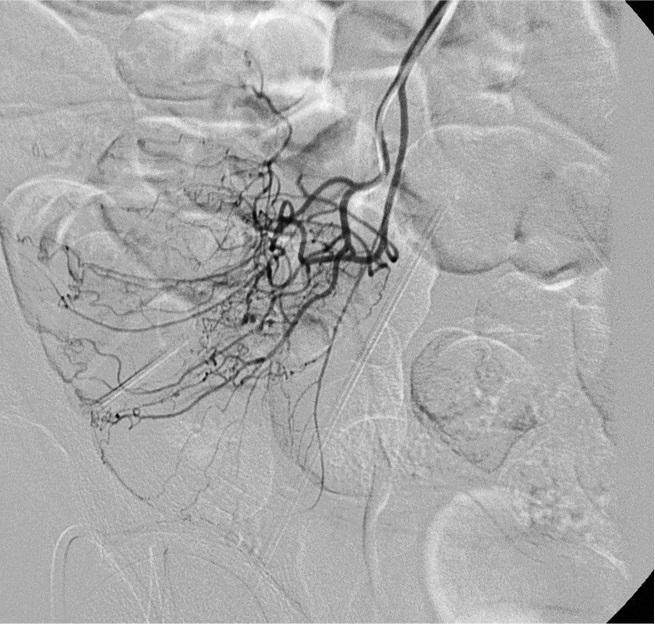

病例二:结肠憩室急性大出血(微导管接近出血)

64岁 男性 无相关病史。因下消化道出血急诊室就诊。考虑到急诊出血情况下效果差,未进行结肠镜检查。CTA 未显示造影剂外溢,但右结肠/回肠大憩室。临床持续出血和生命体征恶化,介入医生会诊决定进行动脉造影。

如果你能用微导管接近出血点,最好的栓塞材料是什么?

造影剂外溢